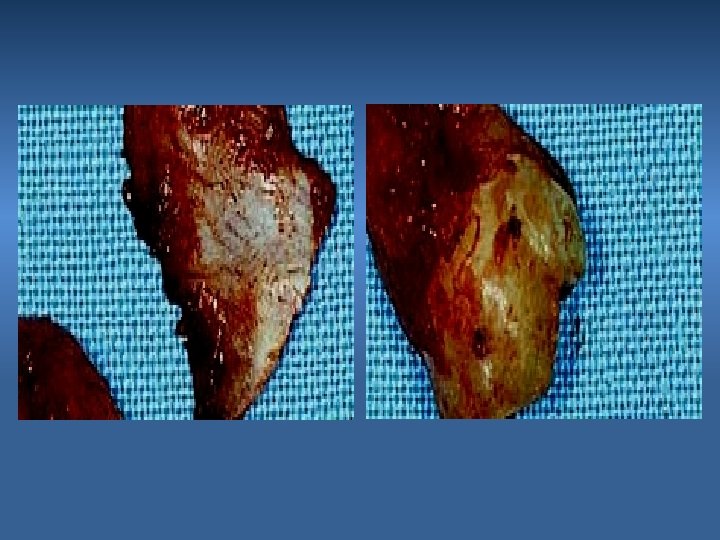

1. Fracture of Alveolar Process Fracture of the Buccal or Lingual Cortex Cause Inadequate exposure & excessive force Prevention Adequate bone removal & eposure

2. Fracture of Maxillary Tuberosity Cause Excessive force Prevention Proper support and controlled force Management If still attached; dissect and remove the tooth If detached; smooth bone edges & suture